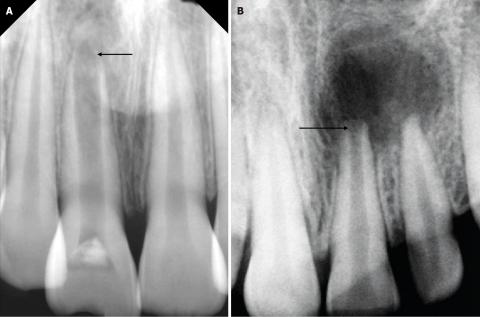

1. Radiolucent Lesion at the Apex

Both Image A and Image B show a dark, well-defined radiolucent area surrounding the root apex of one of the anterior teeth. This appearance is consistent with:

-

Periapical abscess

Periapical cyst

Chronic apical granuloma

Chronic apical periodontitis